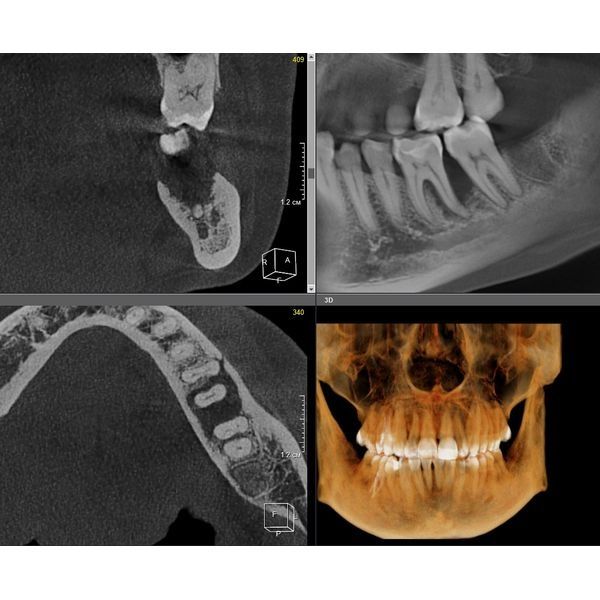

Провели компьютерную томографию — КЛКТ, т. е. 3D-рентген обеих челюстей: выявили неравномерную деструкцию костной ткани в области жевательной группы зубов нижней челюсти до 2/3 длины корня зуба, в области остальных зубов — до 1/3 длины корня.

На пародонтограмме (графическом изображении всех зубов с каждой стороны) визуализировались глубокие пародонтальные карманы в области жевательных зубов нижней челюсти и множественные пародонтальные карманы в области всех зубов верхней челюсти.